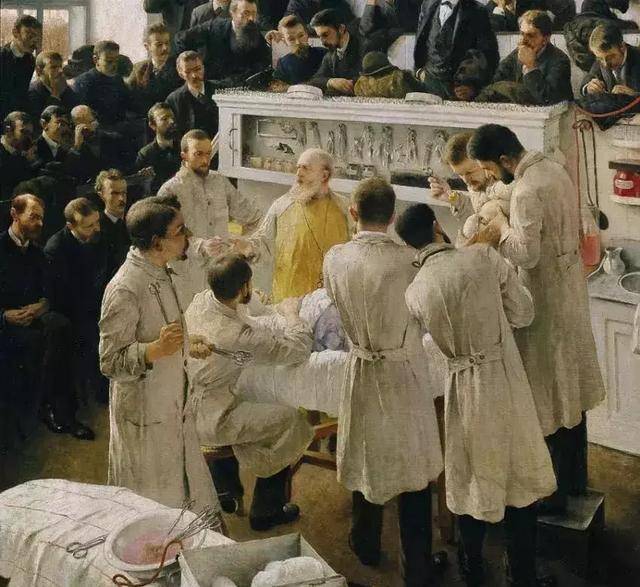

就連「外科之父」西奧多·比爾羅特醫生都曾說過,「在心臟上做手術,是對外科藝術的褻瀆。任何一個試圖進行心臟手術的人,都將落得身敗名裂的下場。」

而「別去惹心臟」,也正是外科秘而不宣的共識。

「外科之父」西奧多·比爾羅特醫生